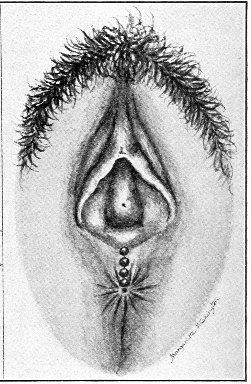

Fig. 18.—Cyst of the right vulvo-vaginal gland (Hirst).

Cysts of the gland may be unilocular if formed at the expense of a single lobule of the gland, or multilocular if several lobules enter into their formation. These cysts may attain the size of the fetal head (Fig. 18).

Cysts of the gland or of the duct are formed by retention of the cyst-contents. The retention is due to occlusion of the duct, usually the result of inflammation. In some cases the duct remains pervious, and the retention is due to the altered character of the secretion of the gland, which becomes too viscous to pass, except under unusual pressure, along the duct.

These cysts contain clear yellow or chocolate-colored 42 fluid. The diagnosis of cyst of the vulvo-vaginal gland is usually not difficult. If we are in doubt in regard to the fluid character of the tumor, this may be determined with the exploring-needle.